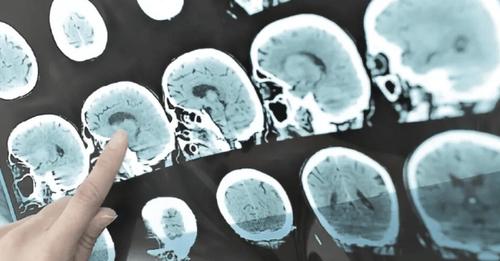

Un medicamento llamado teriflunomida puede retrasar los primeros síntomas en personas cuyas resonancias magnéticas muestran signos de esclerosis múltiple, aunque aún no presenten señales de la enfermedad, según estudio preliminar.

Una afección llamada síndrome radiológicamente aislado se diagnostica en personas que no presentan signos ni síntomas de esclerosis múltiple, pero muestran en una resonancia lesiones en la sustancia blanca del sistema nervioso central similares a las de la esclerosis múltiple.

La responsable de la investigación advierte de que es importante que los profesionales médicos sean cautos a la hora de utilizar la experiencia de la resonancia magnética para diagnosticar esta enfermedad, seleccionando solo a los pacientes con riesgo de desarrollar esclerosis múltiple y no aumentando los diagnósticos erróneos por resonancia magnética.